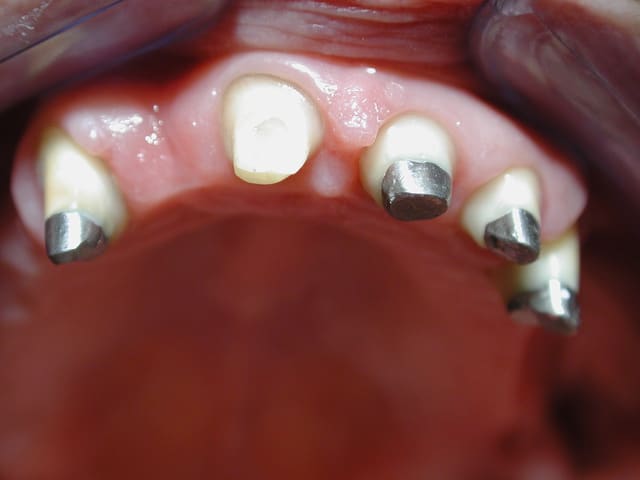

tu preferes quoi ? la photo 1 avec de belles reconstitution de 4 ans et bridge ,ou la photo 2+3 avec des ic haut et bas pour le meme cas refait ?

> tu preferes quoi ? la photo 1 avec de belles reconstitution de 4 ans et bridge

> ,ou la photo 2+3 avec des ic haut et bas pour le meme cas refait ?

Très beau sauvetage grâce à... des IC!

Et oui, il y a beaucoup plus de risque d'avoir des descellements, et des reprises de caries de ce genre, à cause d'un manque de rigidité et ou de résistance mécanique du substrat non reconstitué, ou seulement un composite sans ancrage radiculaire...